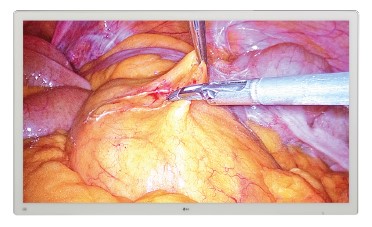

*Pantalla IPS 4K con calidad de imagen excepcional para cirugía.

* HDR10 muestra correctamente las imágenes HDR con claridad.

* Compatible con 12 G-SDI